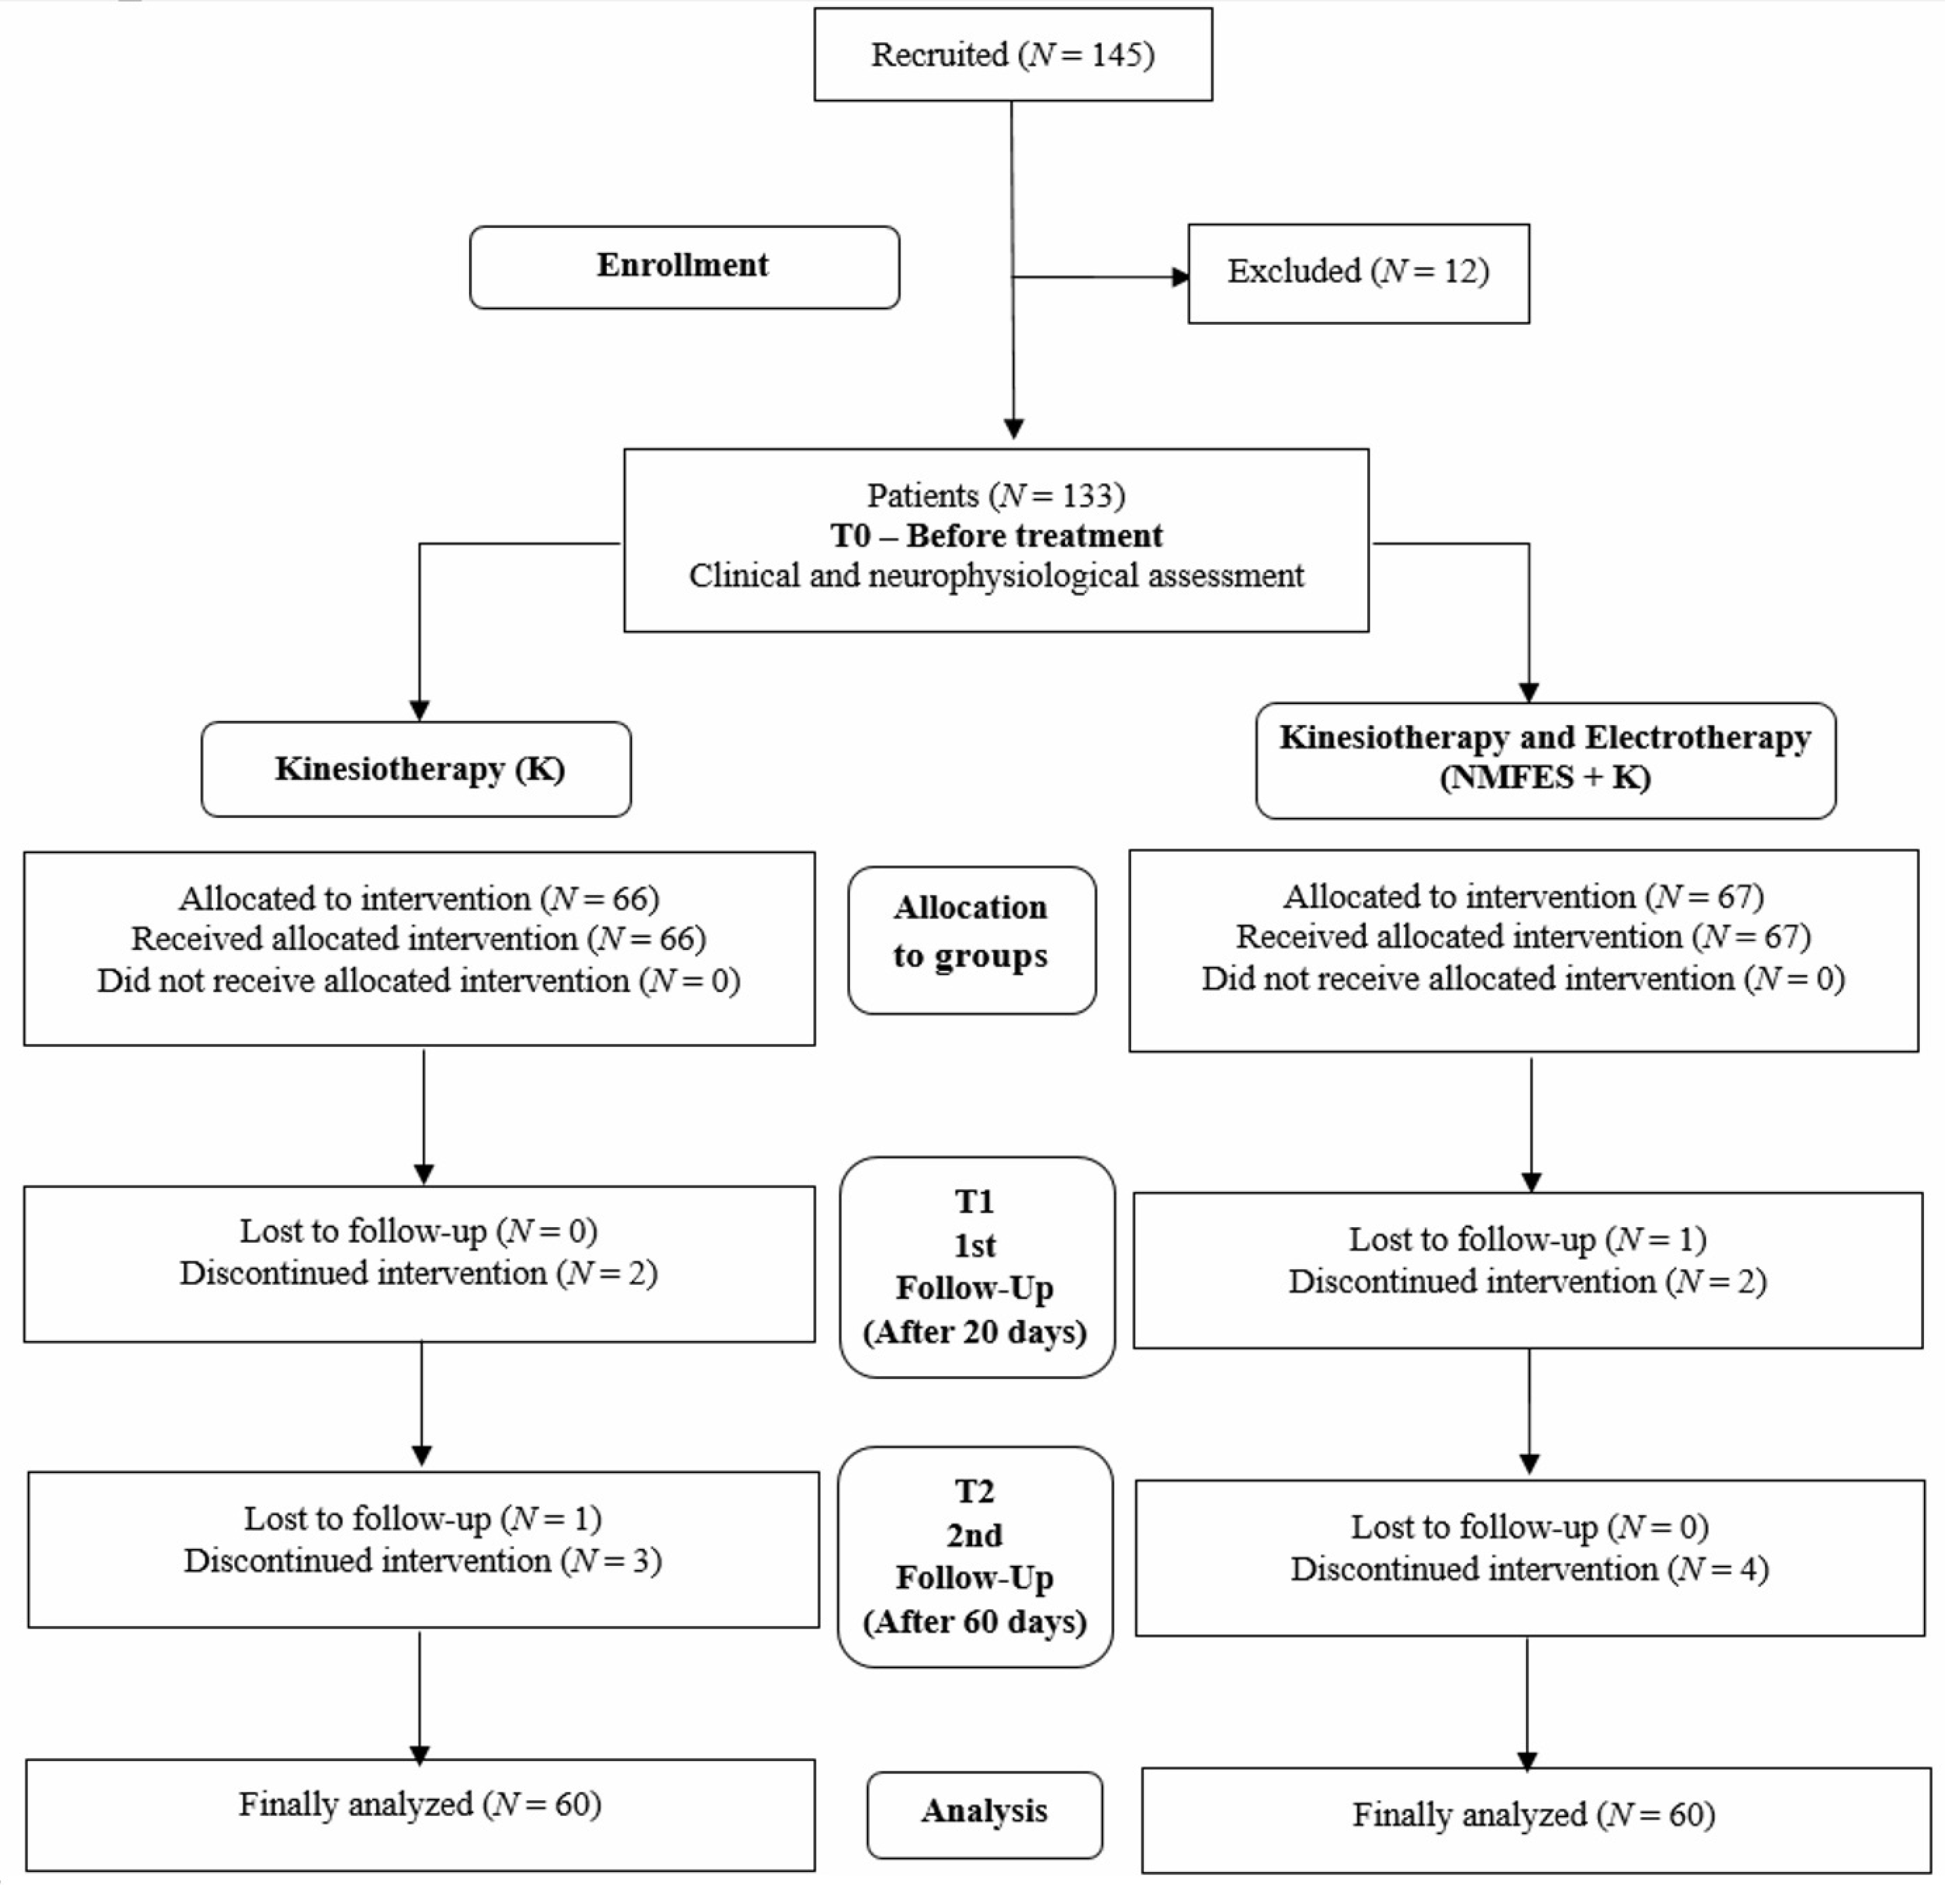

2.1. Subjects and Study Design